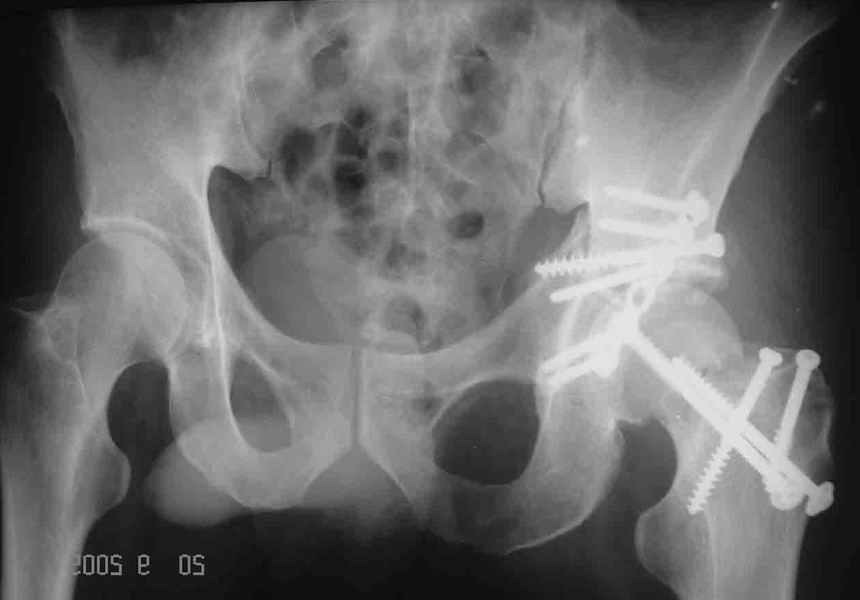

Привет! Вот недавно прооперировали похожий на ваш случай - впадина + шейка (правда у нас впадина поперечный+задний край). После травмы прошло 4 недели. мужчине 46 лет. С такой комбинацией все показания к первичному протезированию. Морально и технически мы к этому уже созрели.Но больной не собрал денег на протез. Выполнили остеосинтез впадины и шейки, прекрасно понимая, что головка вскоре рассосется, мы хотя бы надемся что к этому времени таз срастется, как говорится создали все условия для дальнейшего протезирования (может, и протез в последующем подешевле будет, в смысле, без укрепляющего кольца?). Привет Рункову!

Рунков 27 Сентябрь 2005, 09:57

Привет Алекей! Сделано неплохо, поздравляю, хотя второй винтик можно было бы и подлиннее в шейку загнать! Пара вопроов: доступ такой же? головка была свободной или висела на капсуле?

Отправитель: Алексей Смирнов 27 Сентябрь 2005, 22:35

Согласен, можно было и подлиннее. Доступ такой же - чрезвертельный, только разрез кожи прямой (а не Y, чего то я разницы не ощущаю). Головка была абсолютно свободной (то есть во время остеосинтеза таза лежала в стакане и не мешалась). Шансов, что она прирастет 0,00001%. Хотели даже выбросить, но привинтили как временный биологический протез (читай свободный трансплантат), чтоб на период срастания таза бедро проксимально не ушло (может ортопеды потом спасибо скажут). Ну а у вас первичное протезирование при переломе впадины тоже пока полько в планах?